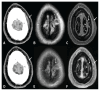

Ostéomyélite syphilitique chez un patient présentant des céphalées et des lésions lytiques